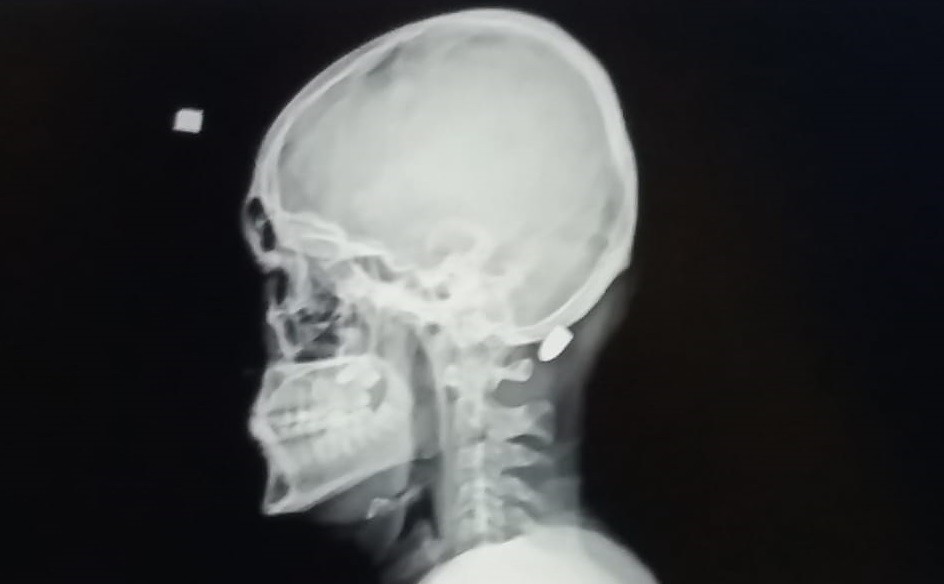

Edinilen bilgiye göre, Karadağ Yaylası’nda dün saat 14.00 sularında 18 yaşındaki Ali Kuleyin’in kafasına nerden atıldığı belli olmayan kurşun isabet etti. Yere yığılan genç yakınları tarafından Vakfıkebir Devlet Hastanesi’ne kaldırıldı. Yapılan operasyonla Kuleyin’in boynuna isabet eden mermi çıkarılırken, gencin sağlık durumunun iyi olduğu öğrenildi. Olayla ilgili soruşturma başlatıldı.